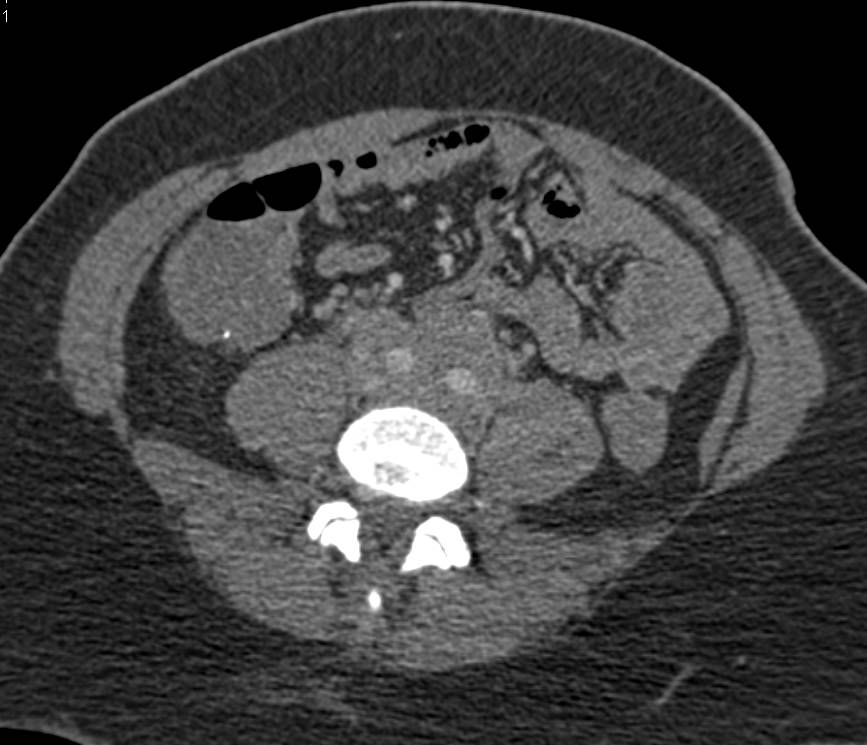

КТ ретроперитонеального фиброза: Изображения и диагностика

Раздел: Мудрость в деталях